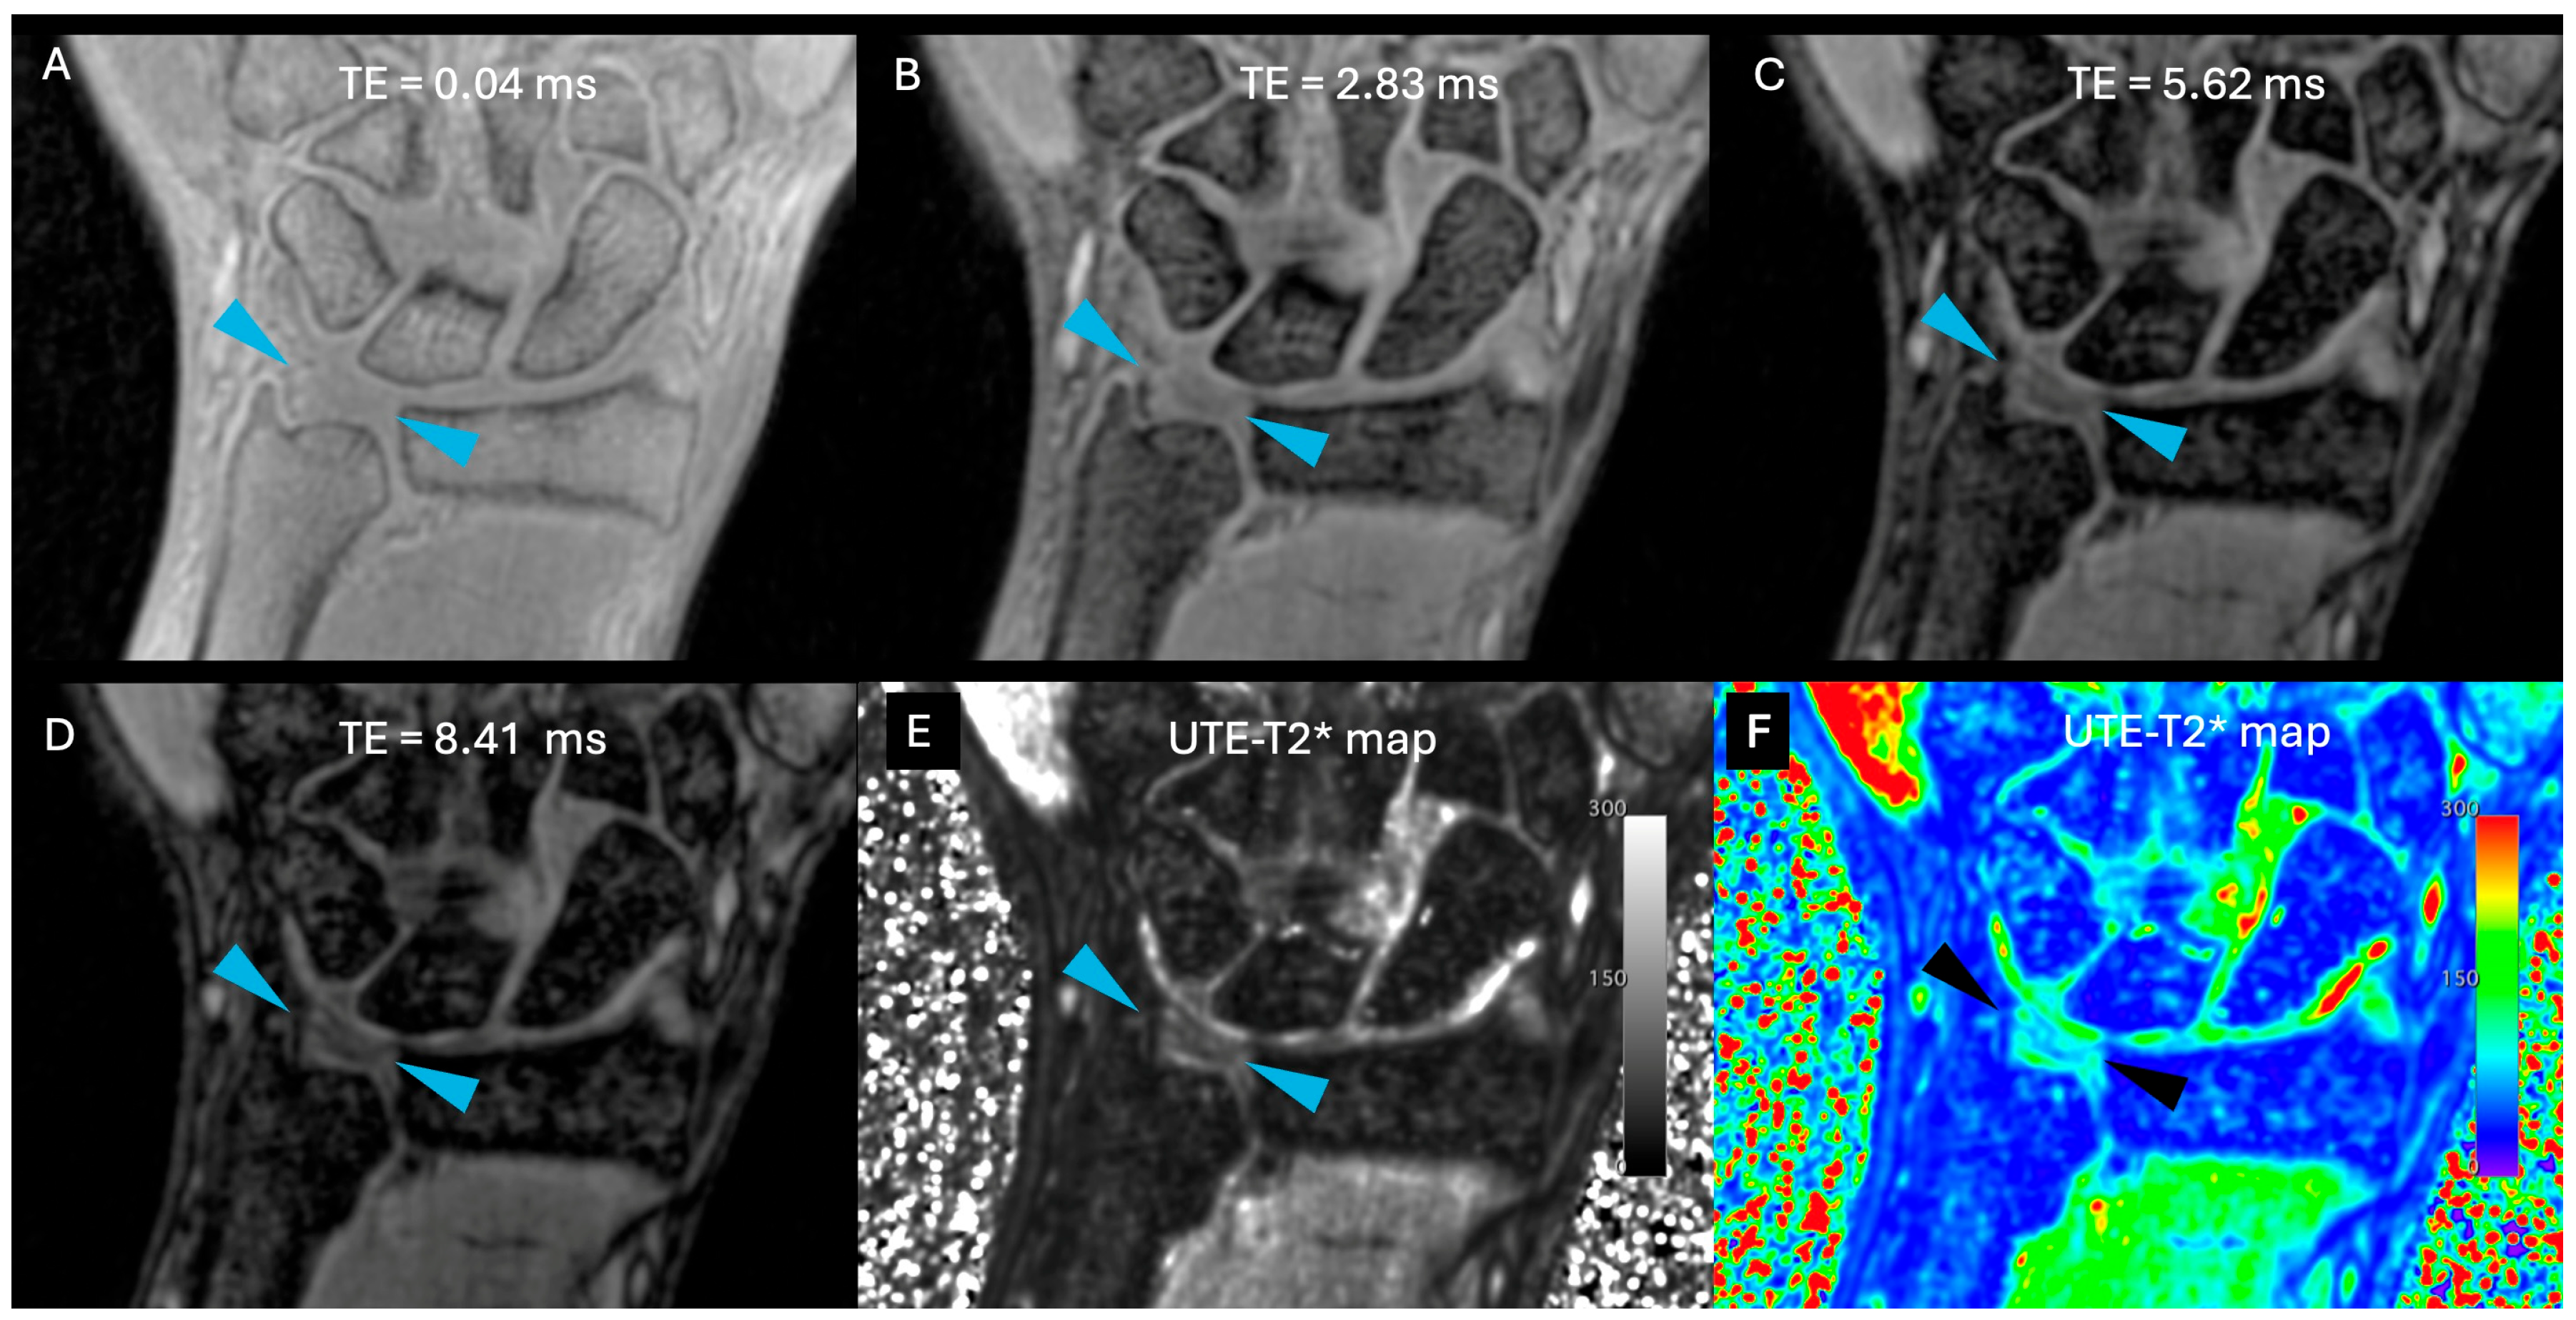

Images were free of artefact, allowing optimal visualization of the TFCC in all cases. No cases of central TFC perforation or additional TFCC injuries were detected. An example of the sequences acquired for one volunteer is shown in Figure 1. Figure 2 presents the multiple echoes of the 3D UTE-T2* mapping sequence along with the resulting UTE-T2* map. TFC segmentation on a single slice of the UTE-T2* map is illustrated in Figure 3 for three volunteers with different ages.

Figure 1. Example of all sequences acquired for the right side of a volunteer. (A) T1 TSE in coronal orientation; (B) PD TSE with fat suppression in coronal orientation; (C) PD TSE with fat suppression in sagittal orientation; (D) 3D PD SPACE with fat suppression in coronal orientation; (E) 3D UTE with fat suppression in coronal orientation; (F) and the first echo of the 3D UTE-T2* mapping sequence in coronal orientation (TE = 0.04 ms). Cortical bone appears hypointense on all sequences. Fluids appear hyperintense on T2- and PD-weighted images and hypointense on T1-weighted image. Fat suppression helps distinguish fluids from fat, as the latter is also hyperintense. Blue arrows indicate TFC.